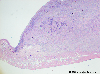

Histology

Histopathological Classifications

Malignant epithelial tumor/Squamous cell carcinoma